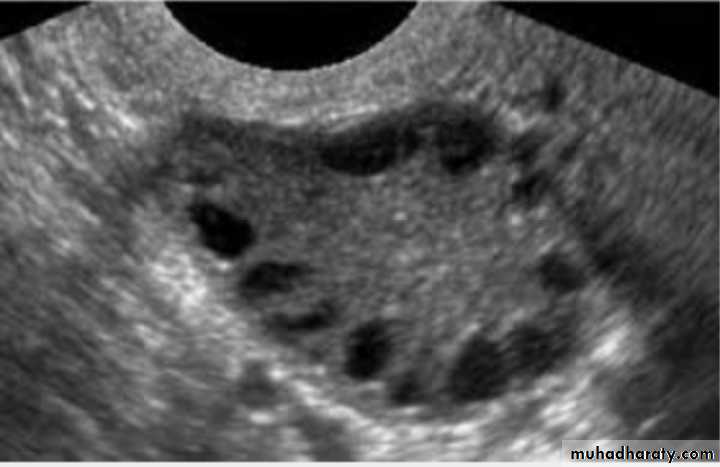

Typical U/S finding in this case : bilateral ovaries containing multiple follicle more than 10 measure 2-9 mm diameter arranged in a neglict apperance with increase stromal thick and overian volum (>10cm3)

U/S:PCOS

PCOS